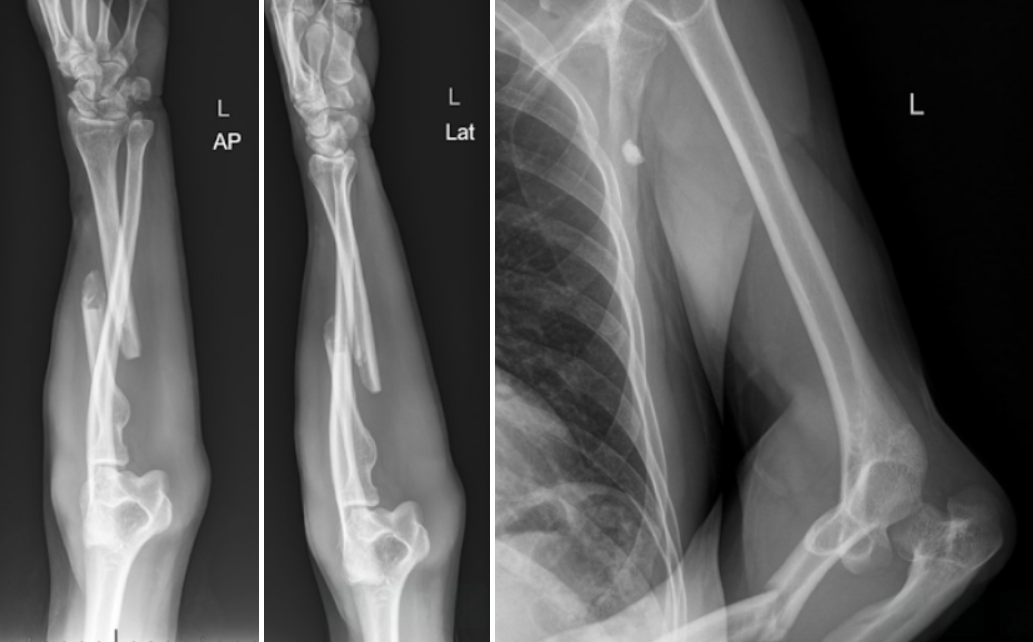

The Floating Elbow

A 30-year-old male with no pertinent medical history presented as a trauma after a motorcycle crash where he was traveling approximately 70 mph. The patient was cut off by another vehicle, and flew off his bike going airborne unknown feet, landing onto his outstretched hands. He is primarily complaining of left arm pain.